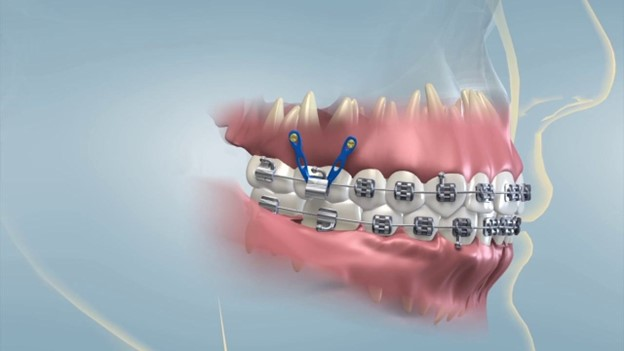

Vít niềng răng (hay còn gọi là minivis chỉnh nha) là một loại vít nhỏ bằng titanium được cắm trực tiếp vào xương hàm nhằm tạo điểm neo cố định trong quá trình chỉnh nha. Không phải ai niềng răng cũng cần cắm vít, phương pháp này thường được chỉ định trong những trường hợp chỉnh nha phức tạp, khi mà phương pháp niềng răng thông thường không đủ lực hoặc không kiểm soát tốt hướng dịch chuyển của răng.

Việc cắm vít khi niềng răng giúp bác sĩ kiểm soát lực kéo tốt hơn, hạn chế tình trạng răng bị xô lệch không đúng hướng. Nhờ có vít chỉnh nha, các ca hô, móm, răng chìa nhiều hoặc cần kéo lùi răng hàm sẽ đạt kết quả cao hơn. Đồng thời với sự hỗ trợ của vít niềng răng sẽ giúp rút ngắn thời gian niềng hơn so với phương pháp thông thường.